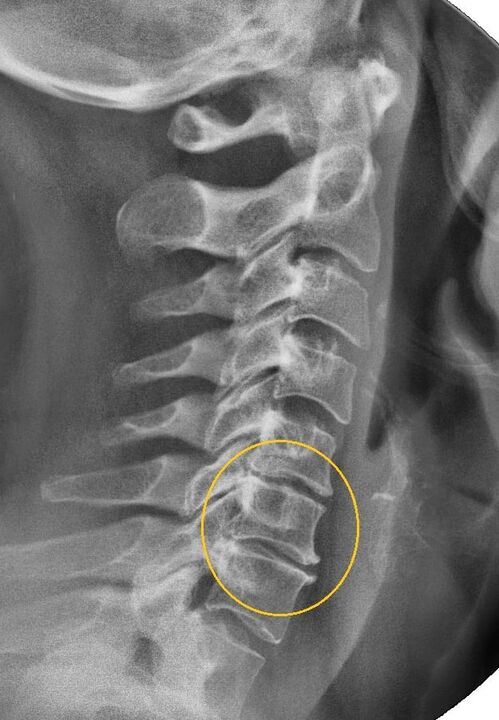

X-ray - shows the stage of the disease, if there is a change in the structure of the bone - arthrosis. MRI and CT scans may also be ordered.